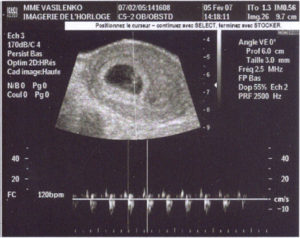

Размер плода на 4 неделе беременности не больше 3 – 4 мм, но он уже надежно закрепился в стенке матки. УЗИ на 4 неделе беременности чаще всего показывает, что зародыш прикрепляется к задней стенке матки, ближе к стороне яичника, из которого вышла яйцеклетка.

УЗИ на 4 неделе беременности позволяет увидеть в яичниках желтое тело, которое увеличено в размерах. На таком раннем сроке это обследование обычно делают в случае проблем с зачатием. С использованием высокоточных аппаратов УЗИ на 4 неделе беременности на задней стенке матки также можно заметить имплантированный зародыш.

Узи плода в 3 недели

Трансвагинальное исследование развития плода в 3 недели никоим образом не расскажет о наличии каких-либо пороков в развитии, и назначается в исключительных случаях:

- существует риск прерывания вынашивания;

- женщина отмечает болевые ощущения в животе или выделения из половых органов;

- желание прервать беременность и необходимость уточнения возраста плода в 3 недели;

- признаки или симптомы внематочного прикрепления плодного яйца.

Срок 3-4 недели беременности: УЗИ

Многие женщины в ожидании зачатия бегут в этот период на ультразвуковое исследование. Стоит отметить, что не всегда доктор может порадовать вас хорошим результатом.

Имплантация плодного яйца в стенку детородного органа может произойти с 3 по 10 день после оплодотворения.

Чем раньше осуществится данное действие, тем быстрее можно будет обнаружить беременность на экране ультразвукового аппарата.

Обследование в этот период проводится при помощи вагинального датчика. Врач наносит на него специальный гель, который позволяет осуществить контакт и увидеть изображение внутренних органов женщины.

В этот период доктор отмечает состояние эндометрия. Также проводится измерение детородного органа в трех плоскостях. Помимо этого врач обследует придатки. В нормальном состоянии к этому сроку в одном из яичников должно находиться желтое тело, которое образовалось после овуляции.

Если уже видно плодное яйцо, то производится его замер. Также врач осматривает его полость и отмечает наличие или отсутствие желточного мешочка, который впоследствии станет зародышем и эмбрионом.